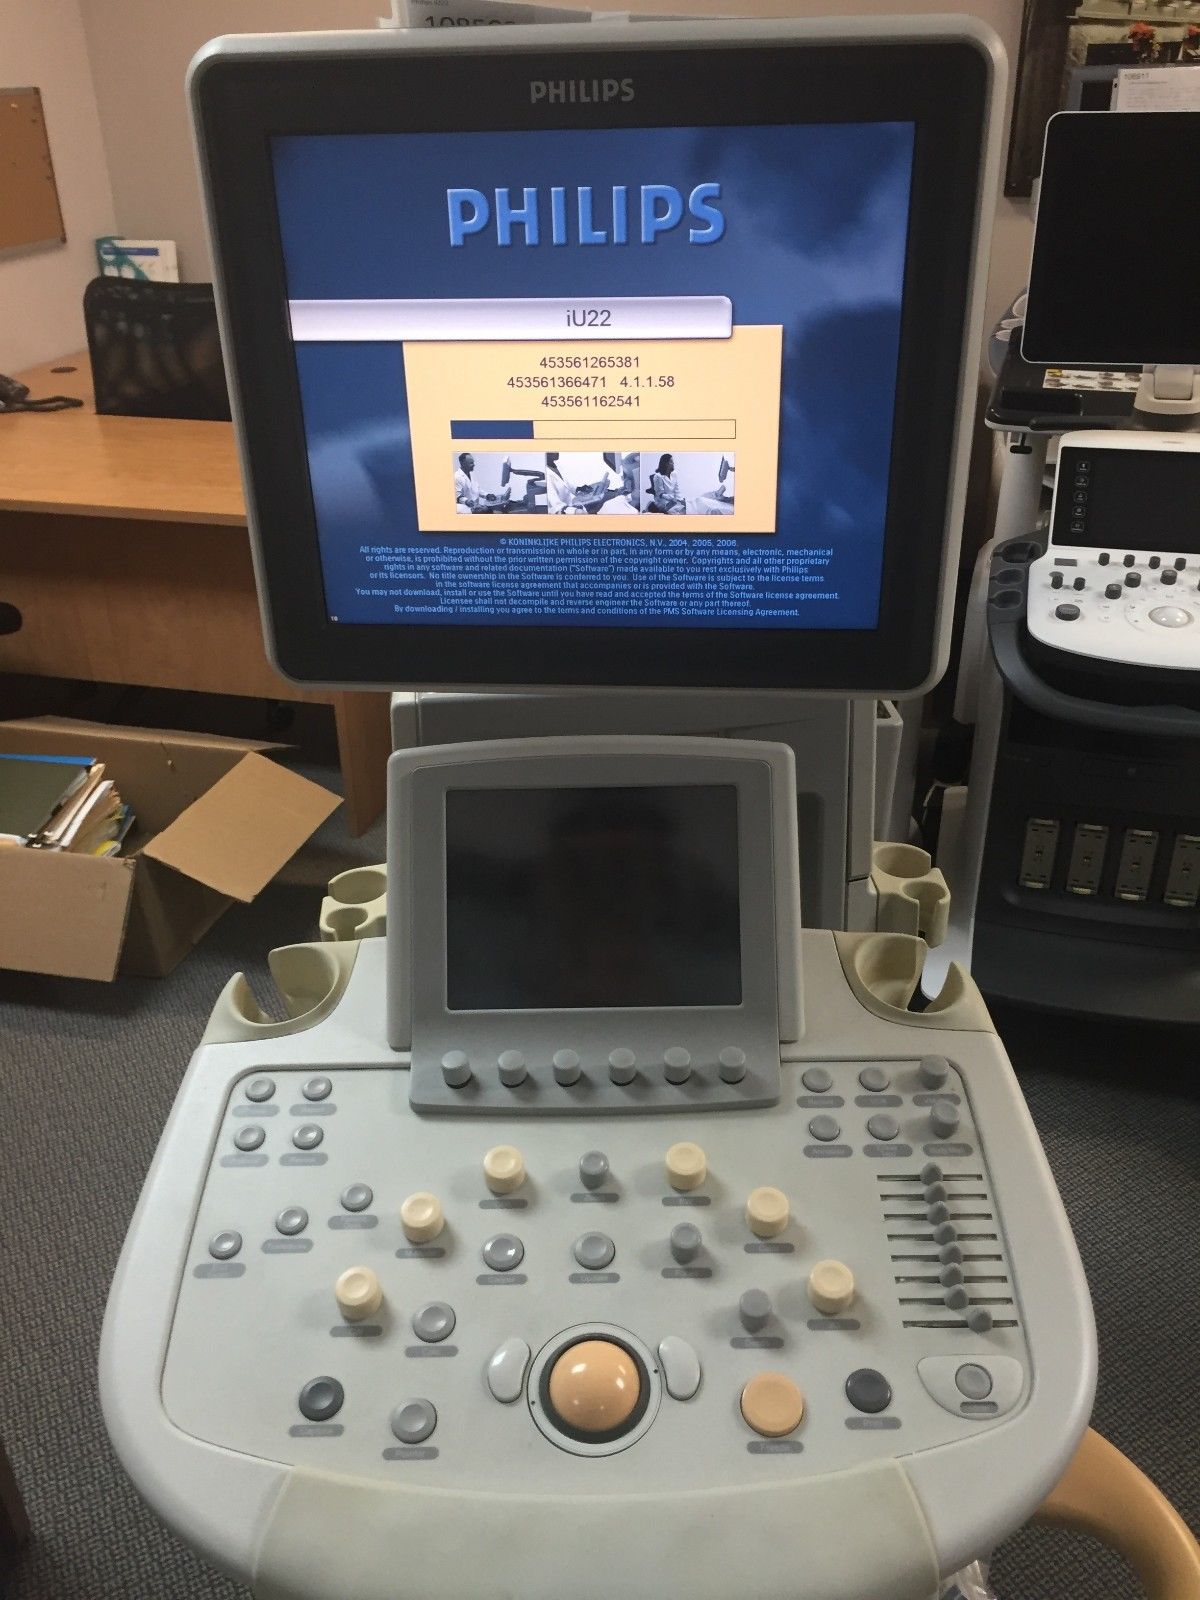

Philips iU22 - A Cart, 3D/4D Ultrasound

Sale price$ 21,585.66